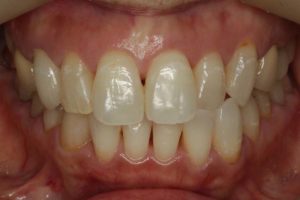

最後に、術前・術後のお写真をご紹介します。

院長のコメント 1年間お疲れさまでした。たくさん治療しましたが、「あっけなくおわりました。」とおっしゃって頂きありがとうございました。当院ではお一人1時間でお約束をお取りしていますので、20分や30分で細かく分けて治療するのに比べ、無駄がなく効率よく進みます。 さらに、治療用の椅子は1台(メインテナンス用の椅子がもう1台)しか置いていませんので、私はお一人の治療に1時間集中できますから、なおさら治療は進みます。 ただ、決して急いでいる訳ではなく、じっくり治療をしているのですが、一つ一つ確実にステップを踏むとミスが少なくなり、その結果治療も早く進んでいくのです。 さて、この患者さんは、ブリッジをやり直す時にそのままブリッジにするかインプラントにするかとても迷われていたのですが、最終的にはインプラントを選択されました。アンケートにもありますように、皆さんが考えている程インプラント治療は痛みを伴うものではありません。今回のケースでも、全く痛みはなく痛み止めを飲むこともなかったそうです。